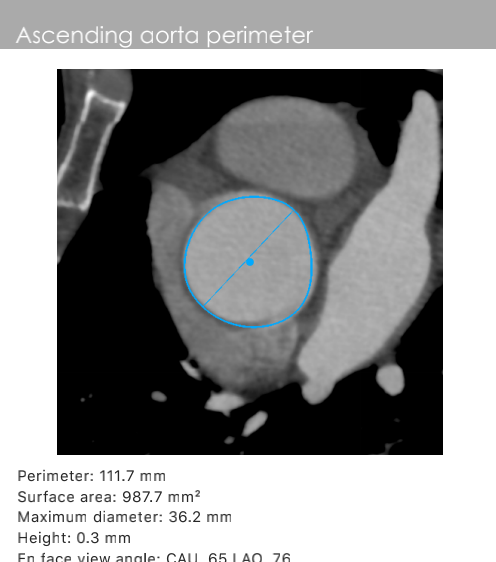

主动脉根部数据:

主动脉瓣环周长82.2mm(平均直径26.1mm),流出道周长89.6mm(平均直径28.5mm),左冠高度:15.4mm,右边冠高:14.9mm,主动脉窦宽28.7mm/33.7mm/34.9mm、STJ周长:93.5mm(平均直径29.7mm)高度22.2mm,升主动脉周长:111.7mm(平均直径35.5mm)。

术前心胸外科、心血管内科、超声科、麻醉科、体外循环、介入室等科室进行了术前讨论和术前策略分析:该患者主动脉瓣属于钙化狭窄的Type0型二叶瓣,左右冠脉同窦,无冠窦可见团状钙化,左右同窦钙化相对较少,主动脉瓣环周长82.2mm、呈现椭圆形,左室流出道周长89.6mm,主动脉窦宽28.7mm/33.7mm/34.9mm、窦宽可,STJ周长93.5mm、高度22.2mm,升主动脉周长111.7mm。患者心室壁明显增厚心尖较薄。左冠高度15.4mm右冠高度14.9mm,双冠高度可。患者右股动脉分叉点位于股骨头下缘,穿刺点内径为8.1mm,血管无明显钙化轻度迂曲。左股动脉分叉点位于股骨头下缘,穿刺点内径为7.8mm,血管无明显钙化轻度迂曲。选择右侧股动脉为主入路,左侧股动脉可作为辅入路;考虑患者主动脉瓣二叶式畸形,钙化严重,采用DOWNSIZE策略,综合评估选择20mm/22mm球囊预扩;患者瓣环周长82.2mm,考虑TAV27型号瓣膜。